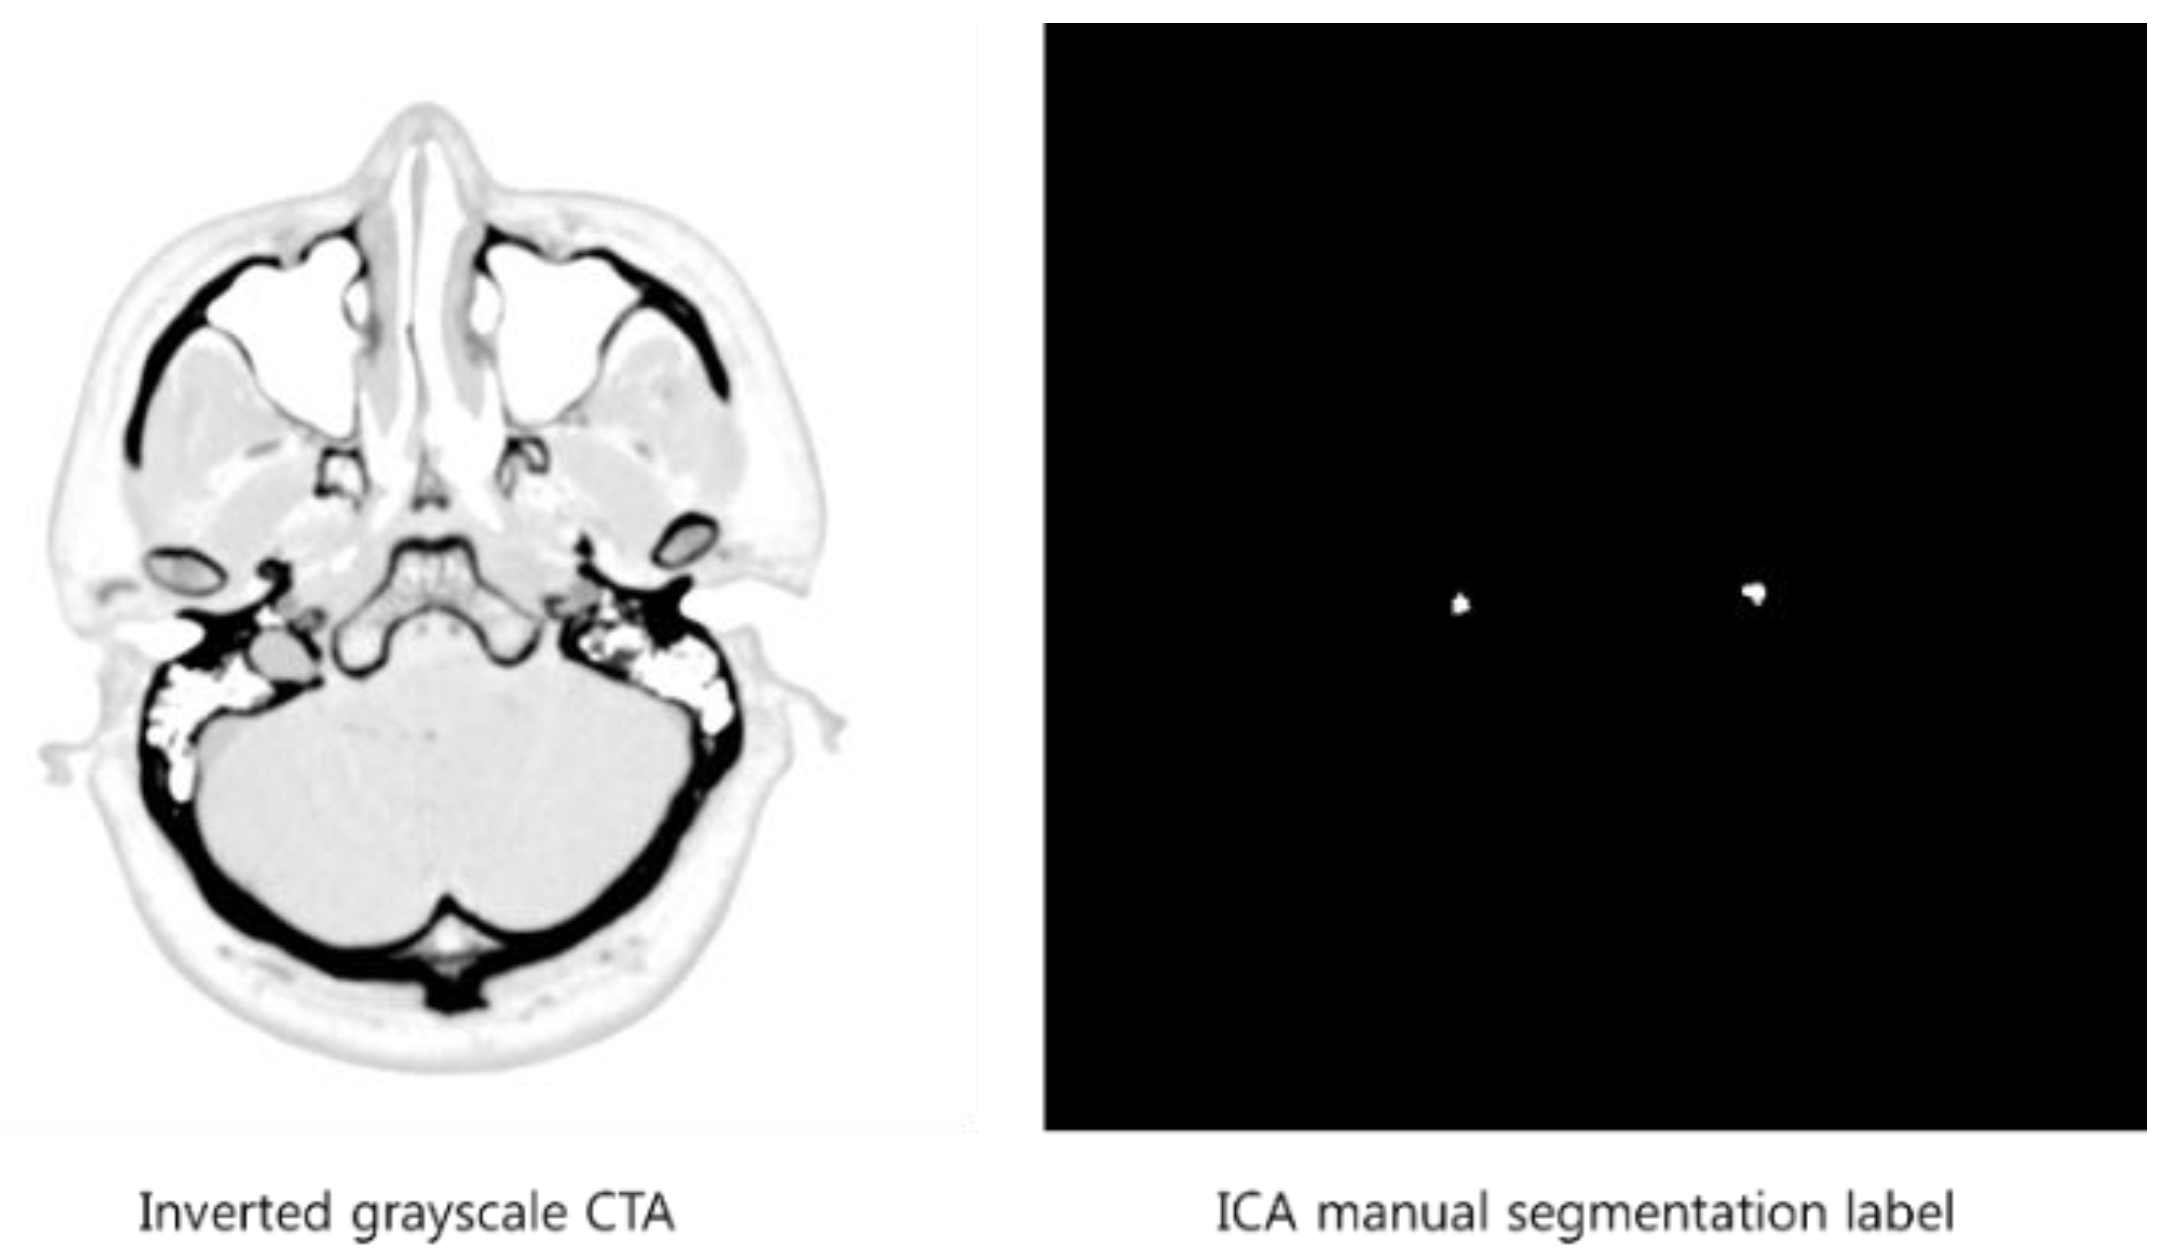

2. Automatic Segmentation Using U-Net

2.2. Preparation of Training Data

2.3. U-Net Training Phase